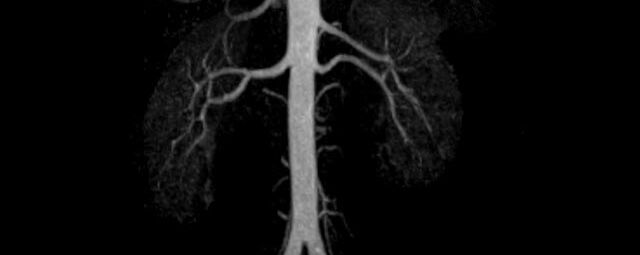

Aorta

• Bauchgefäße

• Erfassung und Verlaufskontrolle bei arteriellen Aneurysmen (Aussackungen der Arterien), vor allem der Bauchaorta

• Darstellung von Gefäßengen an Nierenarterien, Baucharterien und Becken-/Beinarterien